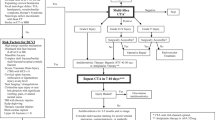

The risk of bias and applicability were assessed using QUADAS-2 tool questions for all included (Fig. 2). Two studies reported no or unclear data on whether patients were consecutively enrolled or randomly selected, or whether a case-control design was avoided [25, 34]. One study systematically applied CTA in patients suspected of BCVI and used DSA in a minority of those patients [23]. They, therefore, anticipated a higher rate of positives in their study population. We also anticipated high risk of bias in patient selection for this study. Three studies clearly stated whether the results of the index test were interpreted without prior knowledge of the results of the reference test [20, 24, 25]. This was also the case for four studies regarding the reference test [20, 24, 25, 35]. In two studies, it was unclear whether all patients were included in the analysis [35, 37]. Overall, there were no concerns for applicability with either of the studies included. The risk of bias was not considered great enough to exclude any study from further analysis.